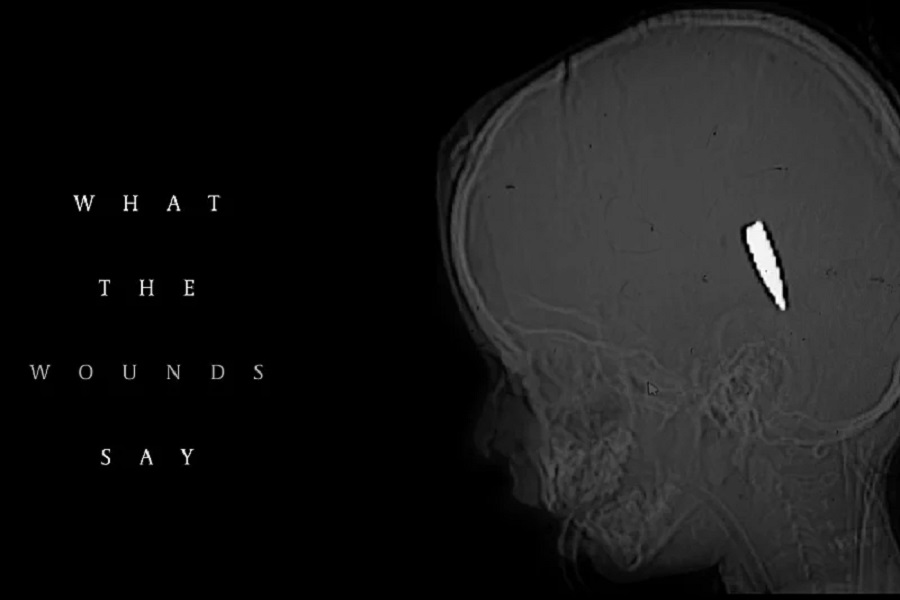

Petnaest njih reklo je da su liječili najmanje 114 djece u dobi od 15 godina ili mlađe s jednom ranom od vatrenog oružja u glavu ili prsa.

Većina te djece umrla je od zadobivenih rana. Slučajevi su dokumentirani između kraja 2023. i sredine 2025. u 10 različitih medicinskih ustanova.

Jedan od doktora, američki traumatolog Feroze Sidhwa, prisjetio se svog prvog dana u Evropskoj bolnici u Gazi u martu 2024. godine, gdje je pronašao četiri dječaka mlađa od 10 godina s identičnim ranama na glavi unutar 48 sati.

Tokom sljedećih 13 dana susreo se s još devetero djece sa sličnim ranama.

Intervjuirani doktori naglasili su da takve rane vjerovatno nisu slučajne. Forenzički stručnjaci koje su konzultirale novine rekli su da uzorak sugeriše ciljanu vatru, moguće snajperima ili dronovima.